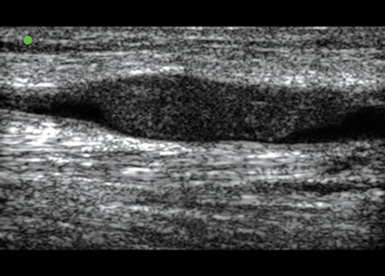

Peripheral IV (PIV) Basilic Vein Thrombus 1 Image